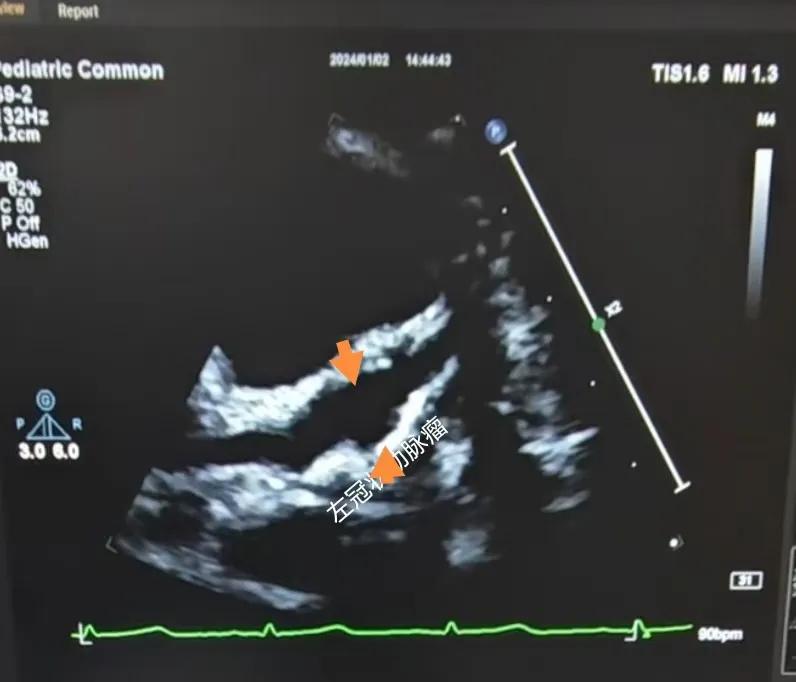

(川崎病患兒:左冠狀動脈瘤)

川崎病是兒童時期一種急性全身非特異性血管炎,對心臟的損害主要是冠狀動脈,可導致冠狀動脈的擴張、冠狀動脈瘤及冠狀動脈血栓,這些損傷可能會引起心肌梗死,目前川崎病已經成為兒童獲得性心臟病的主要原因。心臟超聲診斷川崎病,特別是在臨床癥狀不典型或實驗室檢查結果不明確的情況下。通過心臟超聲,可以觀察到冠狀動脈的擴張情況,這是診斷川崎病的一個關鍵指標。心臟超聲能夠精確測量冠狀動脈的內徑及擴張程度,對于診斷冠狀動脈瘤形成具有特異性。這對于早期診斷和及時治療至關重要。還可以檢測到心臟其他一些并發(fā)癥,如心肌病、心包炎和心律失常等??梢栽u估心臟的整體功能和心肌運動狀態(tài),這有助于判斷疾病的嚴重程度和治療效果。在疾病的恢復期,可以用于監(jiān)測冠狀動脈的恢復情況,并及時發(fā)現可能的復發(fā)或新的并發(fā)癥。

川崎病的超聲診斷標準:

B.冠狀動脈瘤:冠狀動脈內徑>4mm,其與主動脈根部內徑之比>0.3。